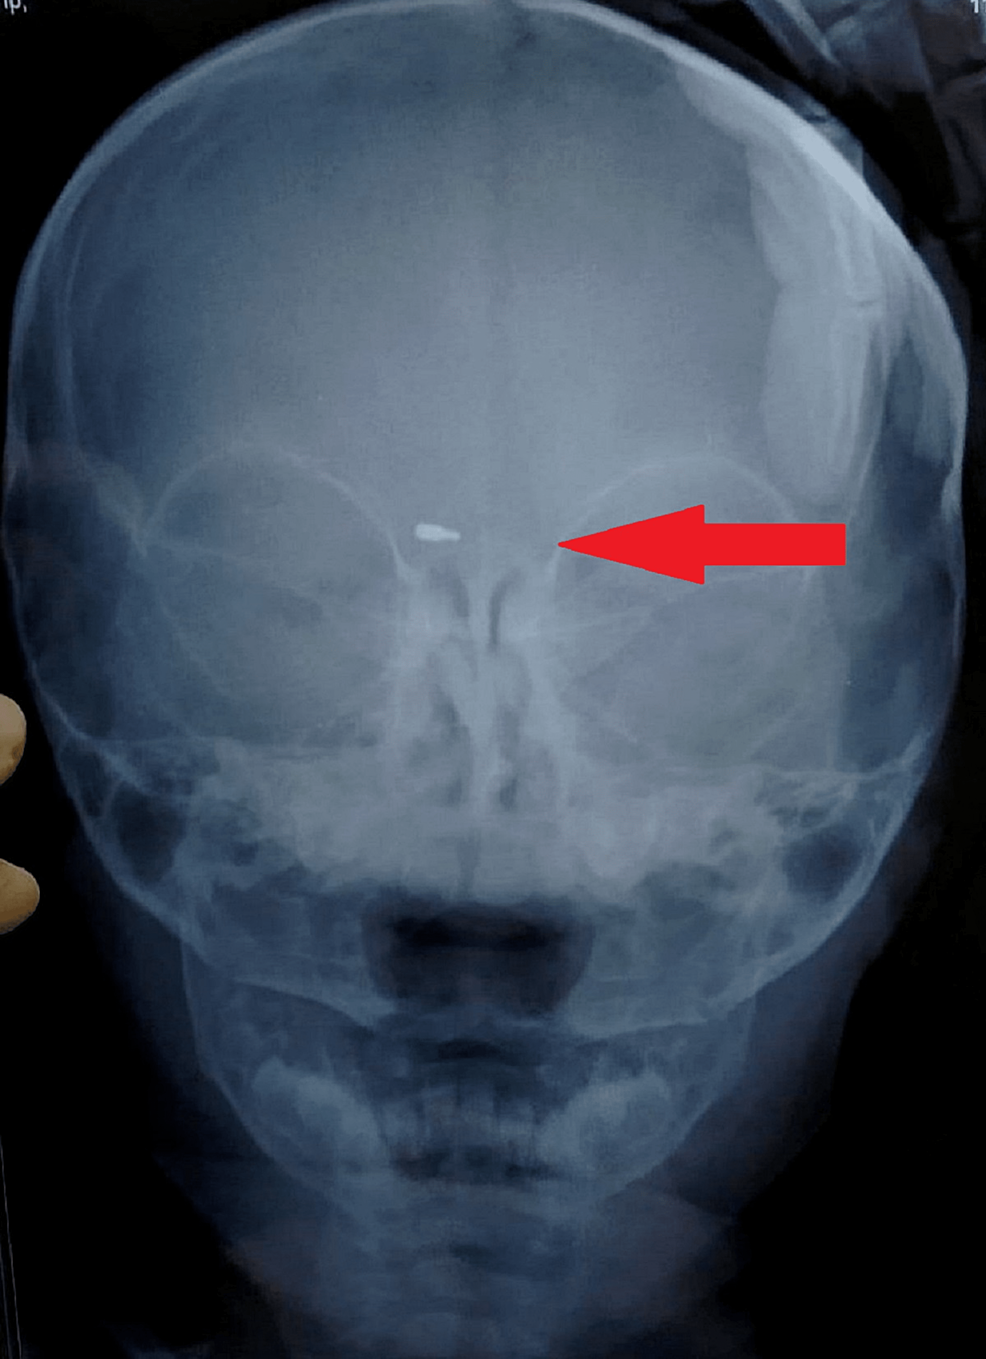

The baby was sent to the ophthalmology department for diagnostic assessment in the tertiary care clinic. A clinical ophthalmic examination revealed an inflamed eye (Figure 1), suggesting pre-septal cellulitis. Routine blood investigations along with an X-ray skull with orbit were advised with a possibility of doubt of lodgment of foreign material. On X-ray, the nib of a pen was found as radiopaque material in the right periorbital soft tissue around 2.5 cm deep from the surface (Figure 2). It was decided to undertake surgical removal of the nib as the surgery was to be performed under general anesthesia, so pediatric and anesthetic fitness was taken along with other routine pre-anesthetic investigations.

Pre-operative intravenous injectable antibiotics were given according to the weight of the child. Surgery was performed to remove the pen nib and the exact site location and the depth of lodgment of the nib of the pen were accessed with the help of a plain X-ray. The incision was made and dissection was done until the pen nib was found. The nib was extracted with the help of artery forceps. Sutures were taken to close the wound.

This present case describes accidental traumatic lodgment of the metallic tip of a ball pen near the eye just above the lachrymal area. As the baby was profusely crying and rubbing the eye, the injury site was left unnoticed and led to misdiagnosis with an eye injury. The patient was clinically examined by various health care providers, including ophthalmologists, ENT surgeons and a pediatrician. But the nib of the pen lodged between the bridge of the eye and nose was left unnoticed by the examining medical professionals or health providers. This is not unusual and is often overlooked. However, an anteroposterior and lateral x-ray of the face revealed a well-defined radiopaque foreign material lodged in the periorbital soft tissue between the eye and nose. Unintentional eye injuries in small children are prevalent. If left unobserved by parents or caretakers, it is challenging to assess as the kids are in distress and pain. Penetrating trauma in or near the eye requires urgent treatment as it can lead to infection and other complications. Early diagnosis and management are helpful to avoid further complications. Parents health care providers and pediatricians should give thorough attention to a crying child with a history of trauma with no apparent clinical findings. Efforts must be made to correlate clinical findings with proper history and other needed investigations. Avoid delaying the management to reduce complications.